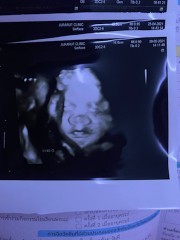

หนูชื่อมะลิค่ะ ยกขาโชว์เลย